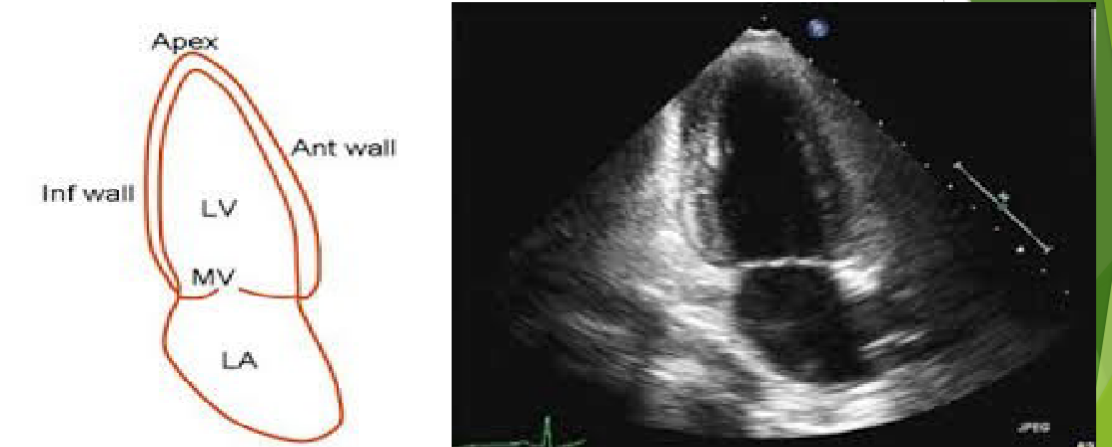

<p>What view is this?</p>

What view is this?

Apical 2 Chamber

5

A2C

A2C View Structures

LV –Left Ventricle

LA –Left Atrium

Mitral valve leaflets

True anterior and inferior LV walls

Left atrial appendage

Descending aorta